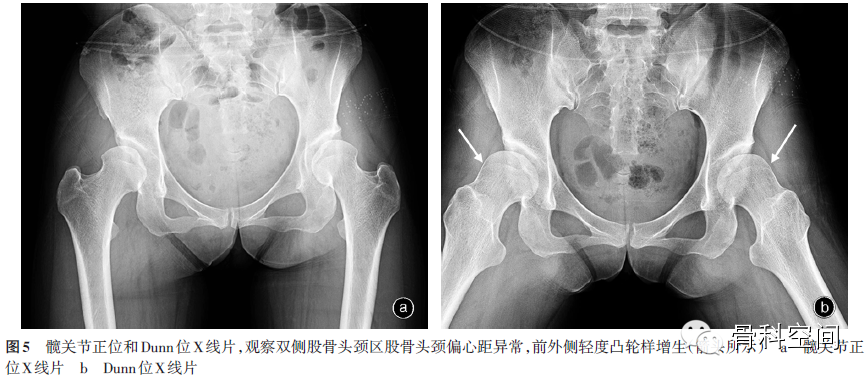

(四)髋关节Dunn位X线片[14](屈髋60°、外展20°位):观察是否存在股骨头颈前方凸轮征(图5),是判断是否需要做前关节囊切开及关节内清理的关键检查。